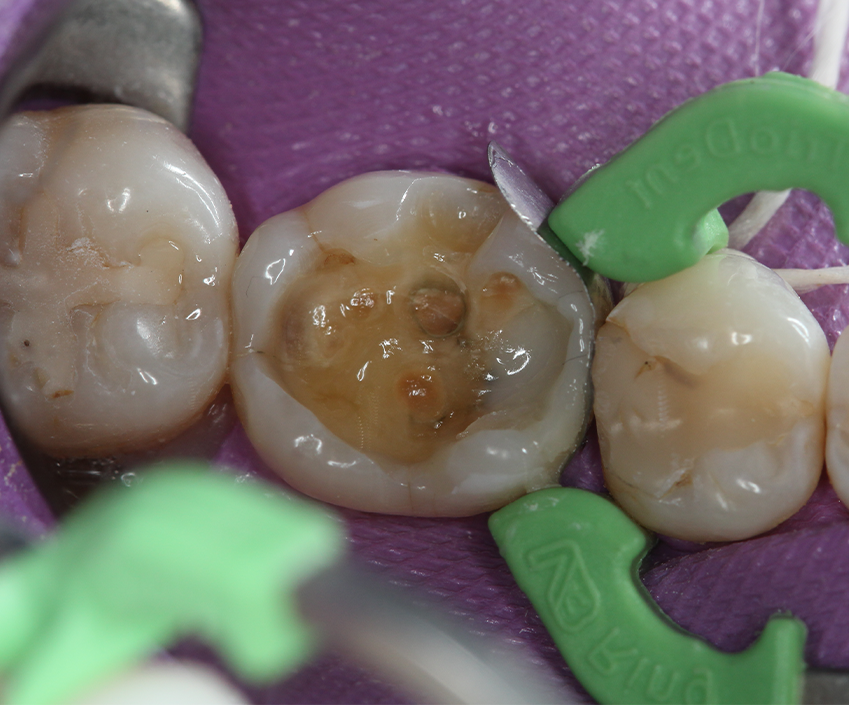

A 36-year-old female patient visited a private office for an annual checkup. Clinical evaluation showed a Class II composite restoration presenting marginal leakage and lack of anatomy and esthetics in tooth #30 (Fig. 1). Due to the patient’s needs and considering the amount of remaining tooth structure, the treatment planned was a direct restoration with resin composite.

Fig. 1 Fig. 2

After initial X-ray (Fig. 2) and rubber dam isolation (Fig. 3), the previous restoration was carefully removed with a 1015 diamond bur (KG Sorensen) in order not to compromise the adjacent tooth. A metal matrix was used for protection. The cavity was cleaned with pumice (Fig. 4).

Fig. 3 Fig. 4